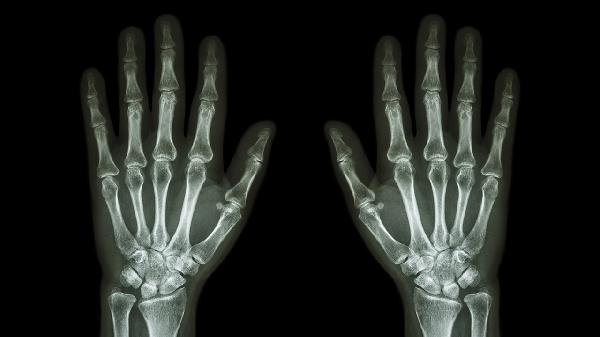

关节软骨退变引发的骨关节炎多见于中老年人,晨起关节僵硬感明显,活动后减轻但过度使用会加重。X线可见关节间隙狭窄或骨赘形成。治疗包括关节保护训练,遵医嘱使用硫酸氨基葡萄糖胶囊、塞来昔布胶囊等药物延缓进展。